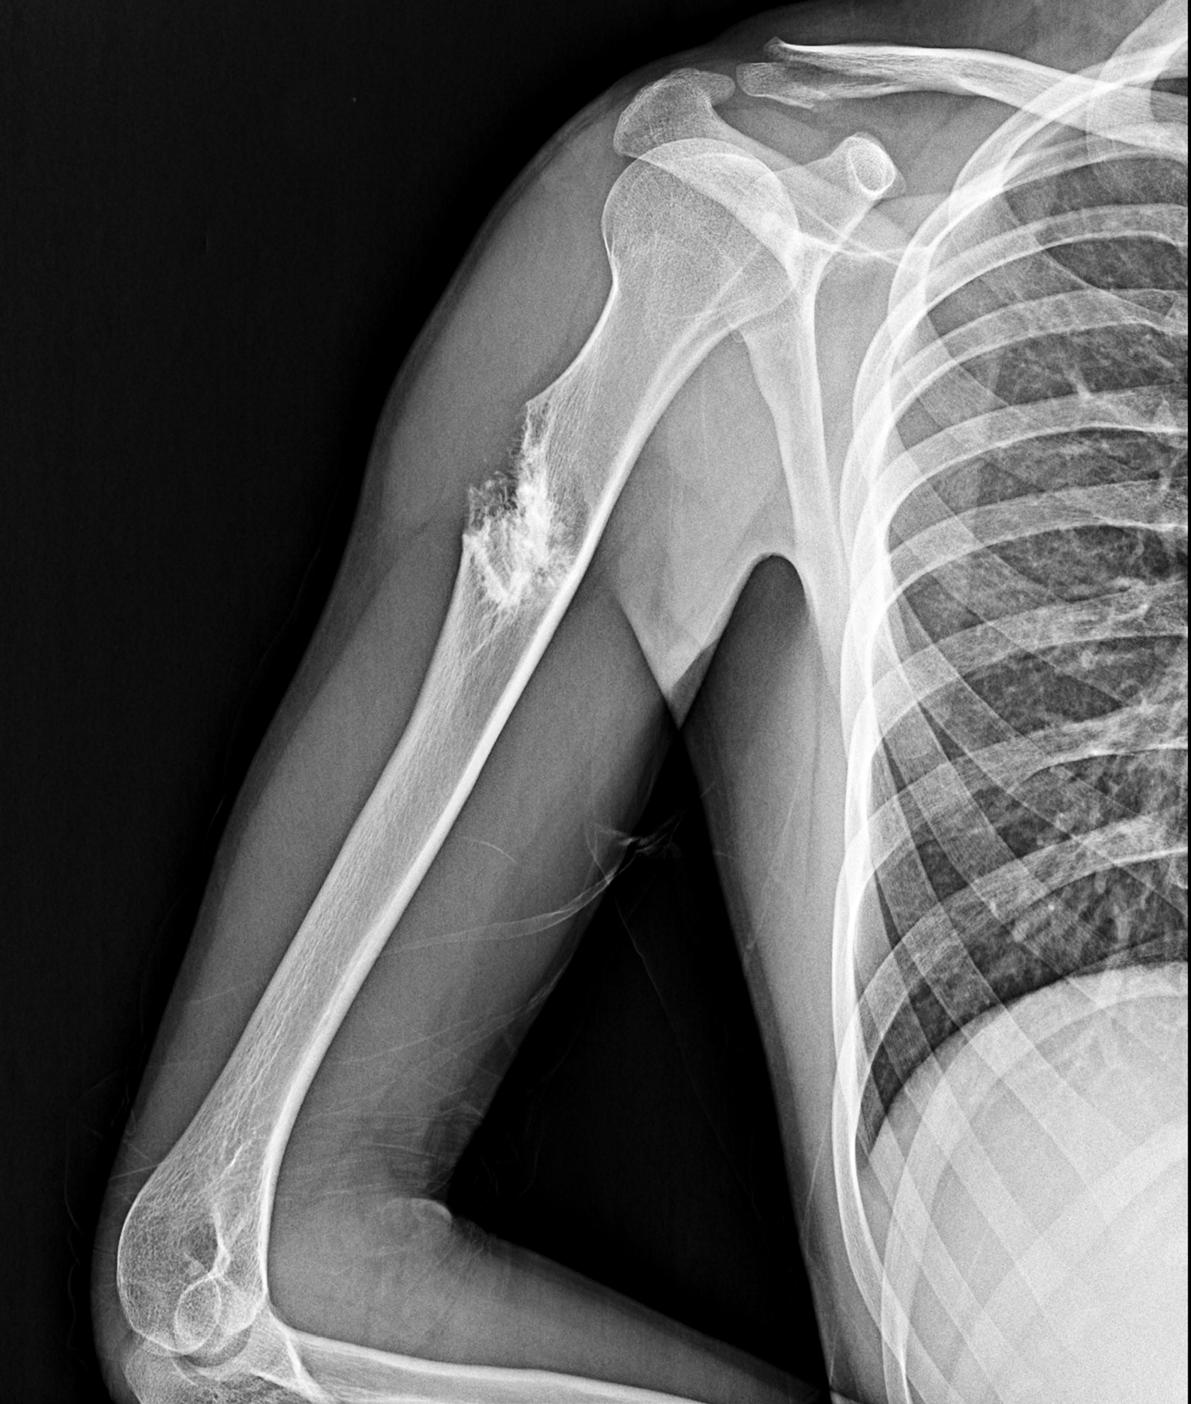

Man versus concrete: who wins?  SNAP!

That question was answered once my shoulder collided with the pavement as my skateboard slid backwards. I pulled myself up to my feet and instantly realized what had happened: I had broken my collarbone. Having never broken a bone before, I didn’t know what to do. All I knew was that I needed medical attention.

I staggered to the cafeteria with my face white as a sheet. After nearly fainting twice, I sat down in a nearby chair. A few minutes later, my friend saw me and rushed me to the nearest urgent care. Once the adrenaline wore off, all I could think about was the searing pain in my shoulder. The nurse helped me back into the X-ray

room. The radiologist took one X-ray and then said she needed to take another of my arm.

“But it’s my shoulder that’s injured.”

“Yes, but I’m seeing something weird in the arm too.”

“Alright.” I didn’t think much of it. All I could think about at this point was my collarbone.

After I was done getting X-rays, I was taken to the examining room. The physician’s assistant walked in to tell me what they saw: “So you’ve definitely broken your collarbone.” This confirmed what I already knew. The next thing she said sent shockwaves through me. “Well, we found a tumor in your right arm.”

Everything after that was a blur. All I remembered was the PA explaining to me what I should do next. I went into a panic and called my parents to make them aware of this crisis. Another friend picked me up and took me back to the dorm and I was still panicking. All I could think about were the what-ifs.

What if it is cancer? What if I

have to drop out of school? What if I lose my arm? What if I die?

A week and an MRI later, it was time for me to go to oncology and get a diagnosis for the tumor in my arm. My parents and I went to Omaha, Nebraska, to the only orthopedic oncologist in the state. We were seated in the examination room, and I almost went into another panic just thinking about what the doctor was about to say.

After what seemed like an eternity of waiting, the doctor came in and started discussing the tumor. He then said the following words: “I’m very confident that this is benign.”

My dad and I let out a simultaneous, relieved “Thank God.” The relief hit my mom so hard she almost threw up. The doctor continued: “We’ll get you an MRI every three months for the next year to be sure nothing changes.”

X-ray of Evan’s bone tumor and clavicle fracture (April 4, 2022) Evan Majors is a sophomore English and communication major from Lincoln, Nebraska.